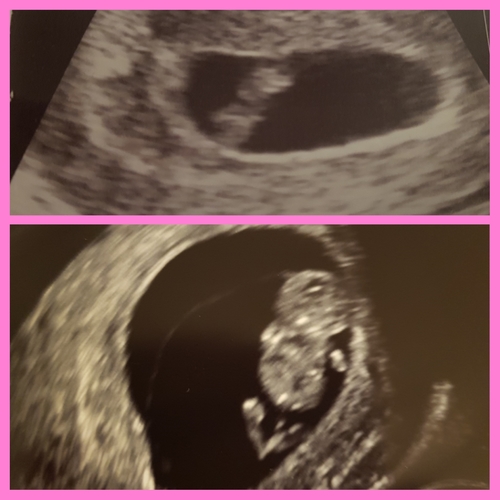

Dit was ons kindje met 8+1 dus voldoende te zien! 😍 hartje zag je goed flikkeren en de arm en beenknopjes kon je ook zien. Het hartje heb ik pas bij 16 weken gehoord. Schijnt ‘veiliger’ voor het kindje te zijn om dit niet voor 12 weken te doen. Ik had m’n termijnecho op 11+1 dus ook toen geen hartje gehoord maar alleen maar gezien.

Dit is de inwendige echo met 8 weken. Met een mooi sterk hartje.

Hartje kan je niet horen met 8 weken, wel kan je het zien kloppen. En dat is net zo magische🥰